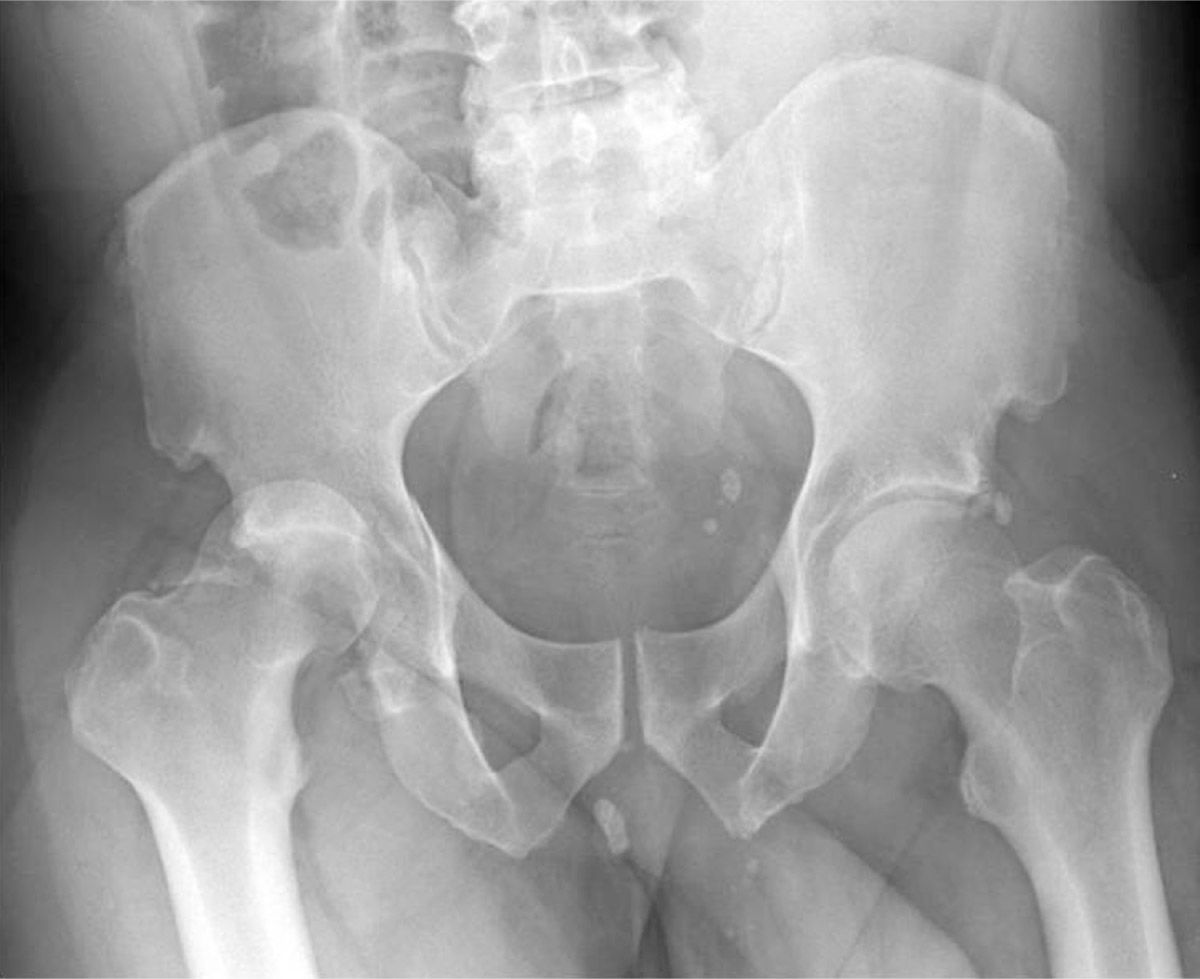

Fixation hip by screw xray, image of xray hip fracture and post

Xray pelvis & hip joint Fracture head of femur (thigh bone Stock Femur Hip Joint Fracture A femoral neck fracture occurs one to two inches from the hip joint. A hip fracture is the medical name for breaking the upper part of your thigh bone (femur) near your hip joint. The risk of hip fracture rises with age. Most hip fractures occur in one of two locations on the long bone that extends from the pelvis. Femur Hip Joint Fracture.